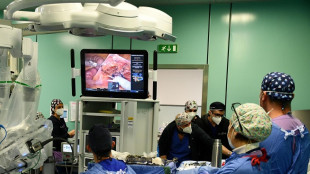

Dall'Ue da 8 milioni per la lotta ai tumori di testa e collo

Progetto a guida italiana, utilizza robotica e IA